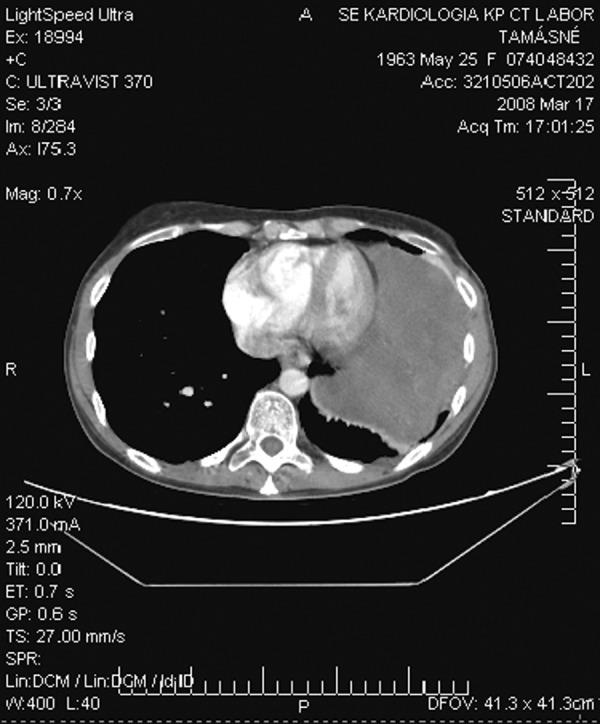

胸内硬纤维瘤的多学科治疗:病例系列和叙述性综述。

Multidisciplinary treatment of intra-thoracic desmoid tumors: case series and narrative review.

Primary intra-thoracic desmoids are exceedingly rare borderline tumors, with 34 reported cases in the English-language literature. The characteristic localized infiltrative growth and the high rate of recurrence can result in life-threatening conditions. Radical surgical resection is considered to be the primary treatment. Achieving negative surgical margins is a challenge. Cases with positive surgical margins are associated with a high rate of local recurrence; therefore, other multimodal approaches play a large role in their therapy.

CASE REPORTS

The authors reviewed the relevant literature and presented examples of long-term follow-up of 3 intra-thoracic desmoid tumour patients, multidisciplinarily treated between 2000 and 2008. All reports of intra-thoracic desmoid tumors that the authors could find on PubMed or in the reference sections of these PubMed located articles were included using the search terms: intra-thoracic, desmoid, aggressive fibromatoses.

原发性胸内硬纤维瘤是一种极为罕见的交界性肿瘤,英文文献中有 34 例报道。其特征性的局限性浸润性生长和高复发率可导致危及生命的情况。根治性手术切除被认为是主要的治疗方法。达到阴性手术切缘是一个挑战。阳性手术切缘的病例与高局部复发率相关;因此,其他多模式方法在其治疗中起着重要作用。

病例报告

作者回顾了相关文献,并介绍了 3 例胸内硬纤维瘤患者的长期随访情况,这些患者于 2000 年至 2008 年间接受了多学科治疗。作者使用以下检索词在 PubMed 或这些 PubMed 定位文章的参考文献部分搜索了所有能找到的胸内硬纤维瘤报告:胸内、硬纤维瘤、侵袭性纤维瘤病。